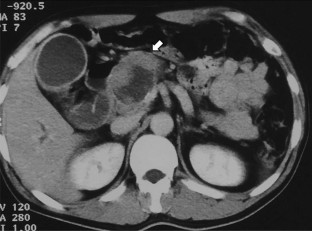

We report a case of a male in his 50 s who underwent pancreaticoduodenectomy for solid pseudopapillary neoplasm (SPN) of the pancreas at 30 years. He developed a liver abscess 15 years after the surgery, and CT scan revealed a swollen retroperitoneum lymph node and a tumor in the liver. Symptoms, including abdominal distension, appetite loss, and epigastric pain, appeared due to lymph node metastasis. Endoscopic ultrasonography-guided fine-needle aspiration against the lymph node revealed SPN recurrence. The tumor had invaded the common hepatic artery, and surgery was not indicated. Chemotherapy of Gemcitabine/nab-Paclitaxel biweekly was performed 8 times; however, no reduction in tumor size was observed, and the patient’s symptoms worsened. Proton beam therapy (67.5 GyE in 25 fractions) was subsequently performed for lymph node metastasis, and led to a gradual reduction in lymph node metastasis, and an improvement in symptoms. No re-expansion of lymph node metastasis has been observed 3 years after proton beam therapy. Since SPN is low malignancy and most cases can be expected to be cured by surgery, there is currently no standard treatment of unresectable SPN. This case is the first report of proton beam therapy for SPN, and was considered to be effective.

Fig. 3